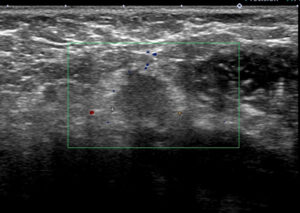

大きなレベルⅡは、レベルⅢに近い部位までせり出し、その奥(図中央)にはレベルⅢが

確認できる。

これらエコーをつなぎ合わせたもの

リンパ節は黄色に表現

大胸筋(茶色)の裏に小胸筋(こげ茶色)

大胸筋の外側にリンパ節2つ、大胸筋の裏にリンパ節1個 これら3個がレベルⅠ

小胸筋裏にリンパ節(これが最大で2㎝)これがレベルⅡ

それより内側(奥)に比較的小さいリンパ節2個 これらがレベルⅢ

色分けすると 赤とオレンジ:レベルⅠ、 黄色:レベルⅡ 、赤(周囲に点線の小さいもの):レベルⅢ